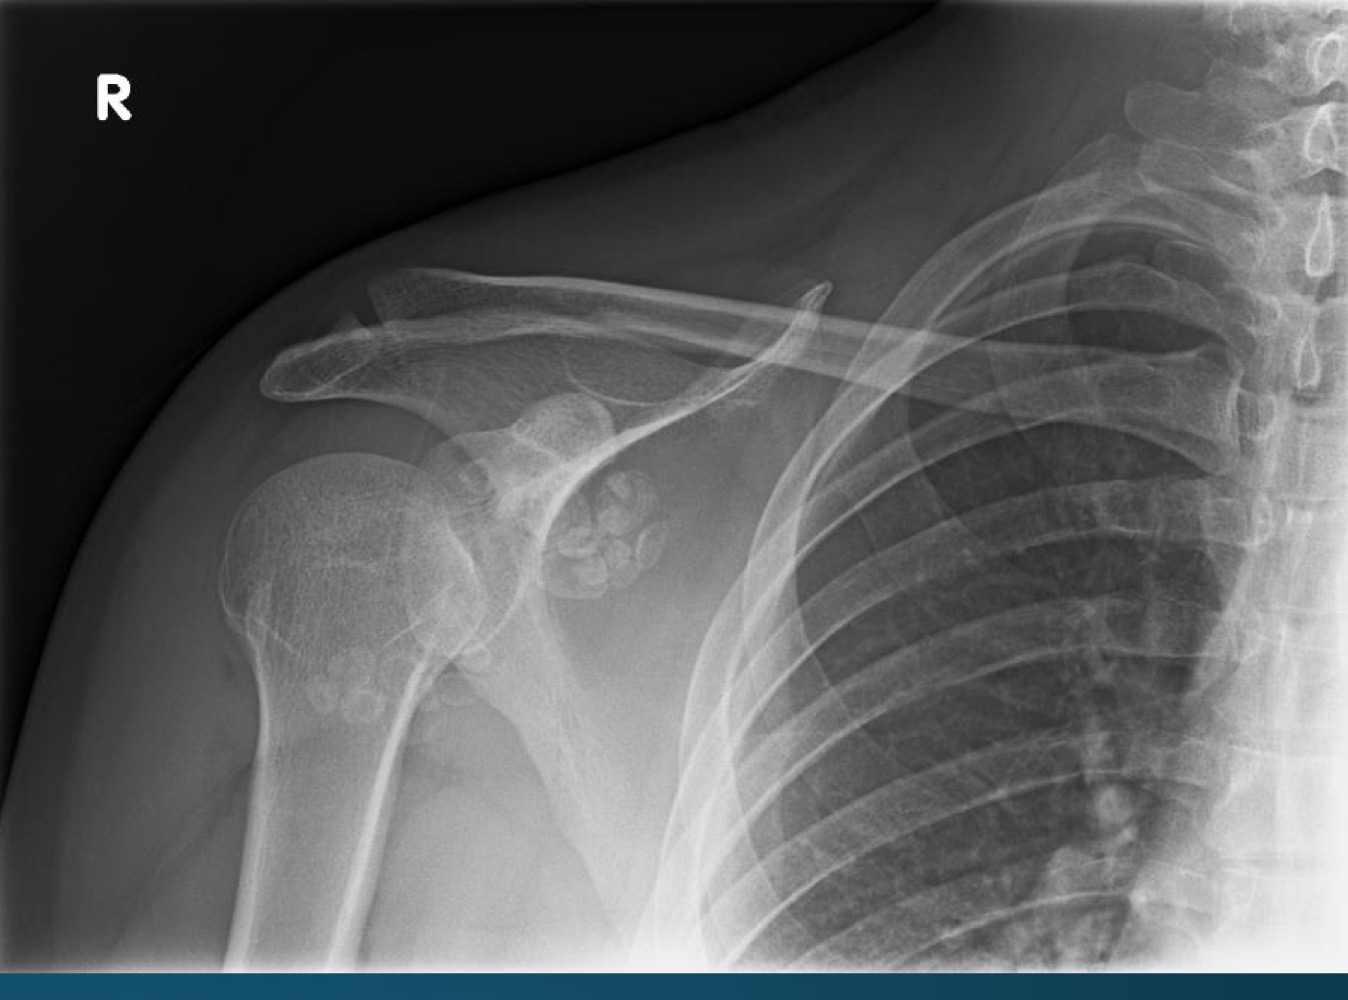

what is this finding?

synovial chondromatosis (SCM)

what is the most commong site for synovical chrondomatosis

knee

loose bodies from synovial chondromatosis might predispose the patient to?

degenerative osteoarthritis

what do you call this feature? what diagnosis is this part of ?

apple core deformity, synovial chondromatosis